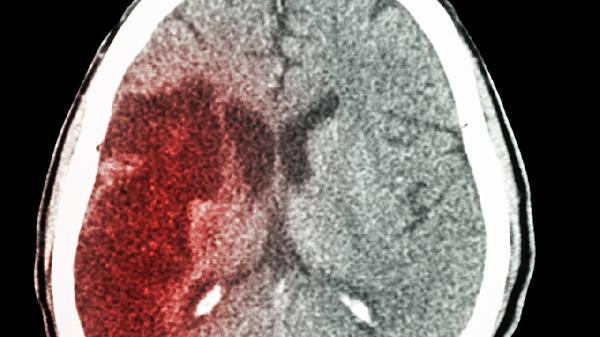

腦出血60毫升時(shí),血腫會(huì)直接壓迫周圍腦組織,導(dǎo)致局部腦功能喪失,表現(xiàn)為偏癱、失語或意識(shí)障礙。隨著出血量增加,腦室系統(tǒng)可能受壓變形,引發(fā)腦脊液循環(huán)障礙。大量血液進(jìn)入蛛網(wǎng)膜下腔會(huì)刺激腦膜,引發(fā)劇烈頭痛和噴射性嘔吐。部分患者可能出現(xiàn)瞳孔不等大、呼吸節(jié)律紊亂等腦干受壓體征。這類患者需立即進(jìn)行頭部CT檢查明確出血部位,并監(jiān)測(cè)生命體征變化。

腦出血60毫升屬于嚴(yán)重情況,通常需要緊急醫(yī)療干預(yù)。腦出血量超過30毫升即可對(duì)腦組織造成顯著壓迫,60毫升出血可能導(dǎo)致顱內(nèi)壓急劇升高、腦疝等致命并發(fā)癥。